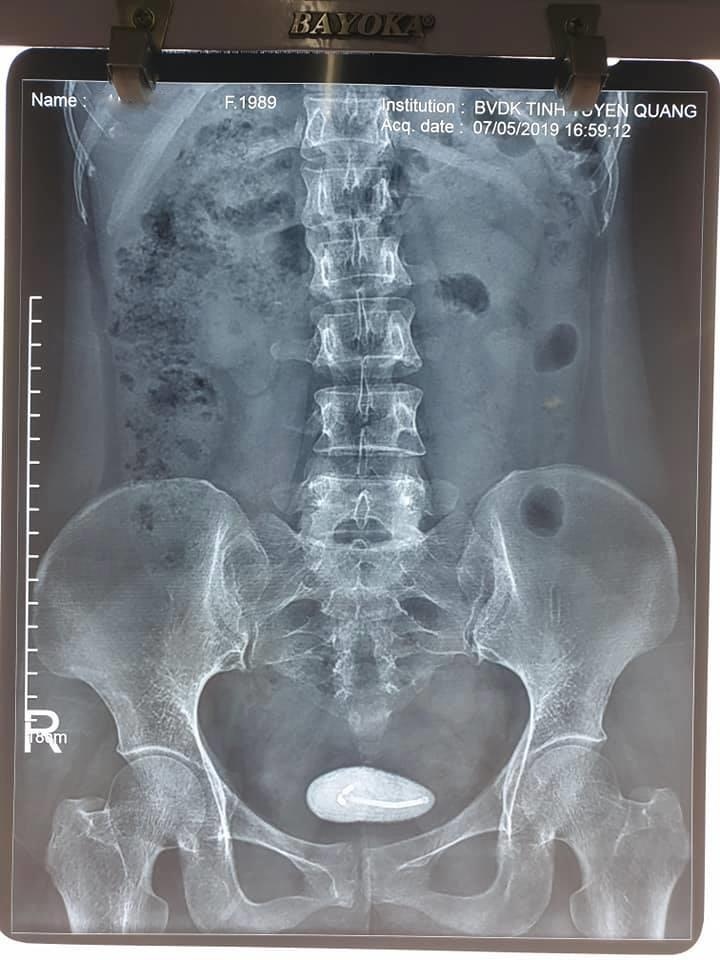

| Hình ảnh vòng tránh thai lạc vào bàng quang nữ bệnh nhân. Ảnh: BSCC. |

Sau khi thăm khám, làm các xét nghiệm cận lâm sàng, bác sĩ chẩn đoán bệnh nhân bị vòng tránh thai lạc vào bàng quang, dẫn đến hình thành sỏi bàng quang, kích thước 5x6 cm.